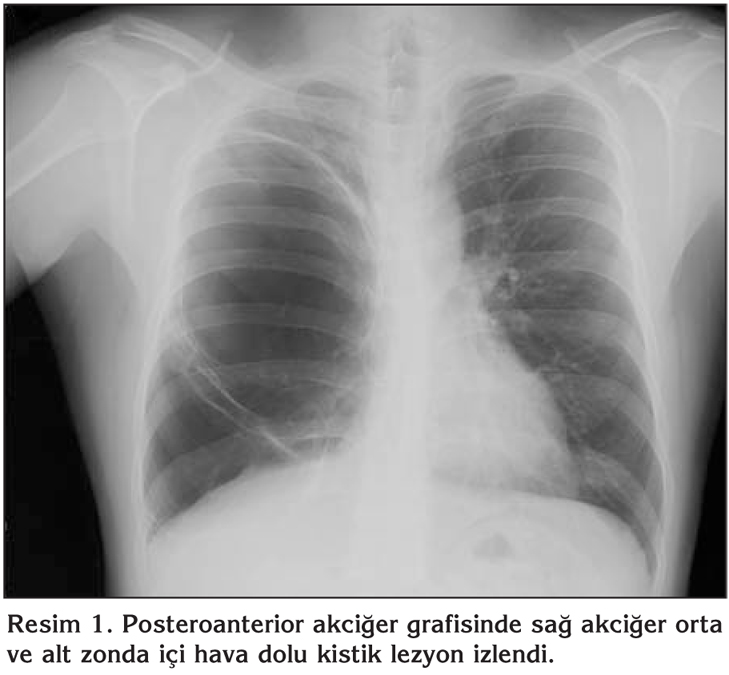

Her Lobdan K Ken Alan Intrapulmoner Bronkojenik Kist Olgusu